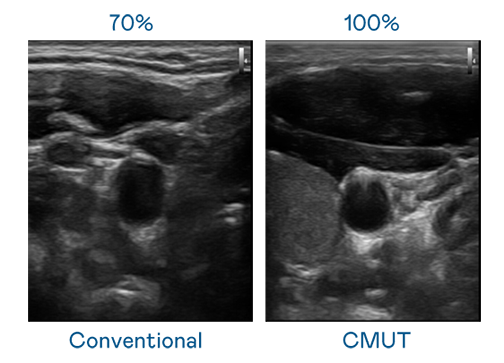

CMUT 技术是一种用电容式微机电元件来产生超音波讯号的技术。与传统 PZT 压电式技术相比,CMUT 频宽增加 30%,更宽频的超音波讯号让影像解析度大幅提升,是实现高影像品质医疗超音波扫描、促进精准医疗发展的关键技术。

大频宽带来超清晰影像

超音波影像的解析度高低,首先取决于探头能发出的讯号频宽。DB真人 CMUT 可提供高清晰的超音波讯号,提供高频宽、高灵敏度、影像纹理细节更高的超音波影像,协助医护人员缩短影像判读时间及利用精准的医疗影像进行诊断。